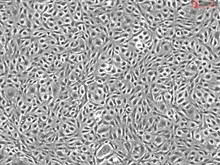

Human Adipose Microvascular Endothelial Cells, Passage 1

Microvascular endothelial cells line blood vessels and contribute to many biological processes such as angiogenesis, coagulation, trafficking of lymphocytes, and the inflammatory response. Microvascular endothelial cells are diverse and have specific cellular characteristics and functions depending on the organ/tissue in which they are located. Adipose tissue is unique because it has the capacity to continually grow throughout adult life. Thus, it has a high level of angiogenesis to provide the extensive vascularization required for adipose tissue. Studies have shown that angiogenesis precedes adipogenesis, implying that microvascular endothelial cells influence the proliferation of preadipocytes. At the same time, microvascular endothelial cell growth is stimulated by adipocyte secreted VEGG, suggesting a complex paracrine relationship between microvascular endothelial cells and preadipocytes during tissue development. (SC7200)